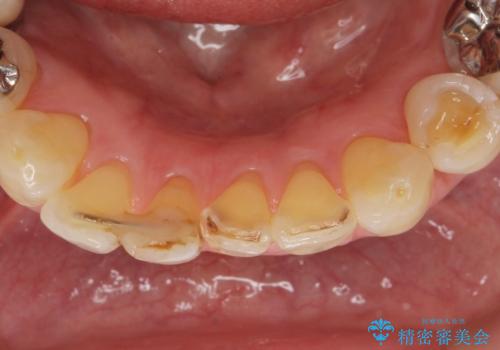

- 下の前歯が欠けてぐらぐらすることを主訴に来院された患者様です。

以前行った奥歯の治療により下顎前歯の動揺は改善傾向にあり顕著ではなかったのですが、欠けて黒くなっていることと少しの動揺が気になるとのことでした。

元気なうちに治療しておきたいという患者様の強いご希望により、下顎前歯の連結補綴と欠けている小臼歯の補綴治療を行いました。